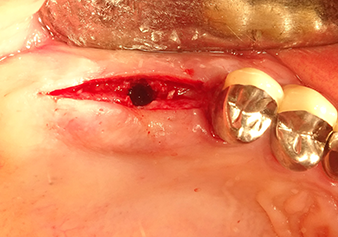

Una paziente di 49 anni, non fumatrice e con un'anamnesi priva di elementi rilevanti, è stata indirizzata al nostro studio di chirurgia orale per l'estrazione chirurgica del dente 16 ed il successivo impianto. Dopo l'estrazione, la paziente ha accusato dei lievi dolori causati dalla sinusite, motivo per cui abbiamo inizialmente aspettato sei mesi prima di procedere con l'intervento. L'altezza ossea residua in corrispondenza della posizione dell'impianto misurava 3-4 mm (Fig. 1 e 2).